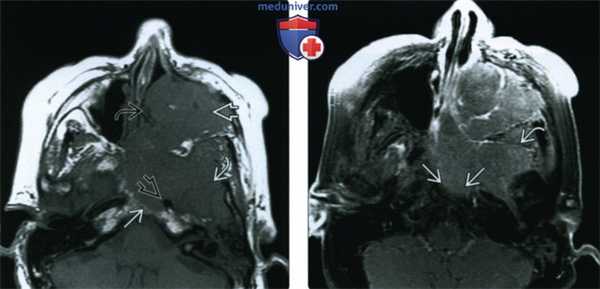

(Слева) При аксиальной МРТ Т1 определяется антральный ПКР очень большого размера с распространением в полость носа, подвисочную ямку и скат. Опухоль окружает левую внутреннюю сонную артерию но потоковое выпадение сигнала в ней сохранено.

(Справа) При аксиальной МРТ Т1 С+ FS определяется рак верхнечелюстной пазухи, равномерно накапливающий контраст, без явных зон некроза. Обратите внимание на инвазию ската и диффузную инфильтрацию жевательных мышц.